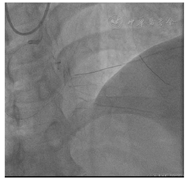

2022年6月21日行RCA-CTO介入治疗,双桡动脉穿刺,左侧桡动脉植入6F动脉鞘管,右侧桡动脉植入7F动脉薄壁鞘管,经左侧桡动脉鞘送入6F EBU 4.0至左冠状动脉开口,经右侧桡动脉鞘送入7 F SAL 1.5至右冠状动脉开口,双侧造影显示RCA-CTO近段及远端血管床及侧支循环(图5)。

经前向指引导管(7 F SAL1.5)操控Finecross130微导管及XT-R导丝不能前向进入RCA远段,更换指引导丝XT-A、Gaia Second、Pilot 150仍不能前向进入RCA远段,对侧造影显示与远段血管床偏离(图6)。